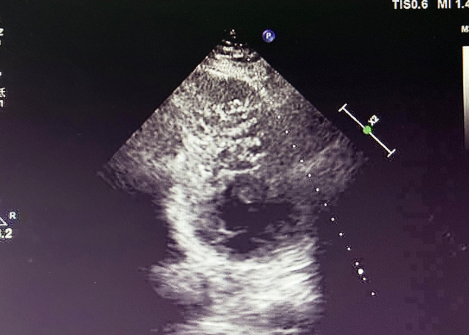

入院后,患者接受超聲心動圖檢查,結(jié)果顯示左心室心肌呈典型 “海綿樣” 改變,可見多發(fā)、粗大的肌小梁和深陷的隱窩,非致密化心肌層與致密化心肌層比值(NC/C)>2.3,完全符合左心室心肌致密化不全(LVNC)的超聲診斷標準。

LVNC 的超聲表現(xiàn)

(1)特征性表現(xiàn)左心室壁明顯增厚,內(nèi)層心肌呈 “網(wǎng)狀” 疏松結(jié)構(gòu),外層致密心肌變薄,血流灌注顯示隱窩內(nèi)血流緩慢,這種情況容易形成血栓。(2)診斷標準(Jenni 標準)收縮末期非致密化心肌層與致密層厚度比 > 2,可見深陷的肌小梁間隱窩與心室腔交通。